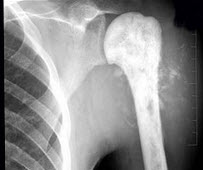

29、单项选择题

男,28岁,右上臂肿胀、疼痛,结合图像,最可能的诊断是()

A.骨肉瘤

B.成骨性骨转移瘤

C.化脓性骨髓炎

D.滑膜肉瘤

E.骨巨细胞瘤